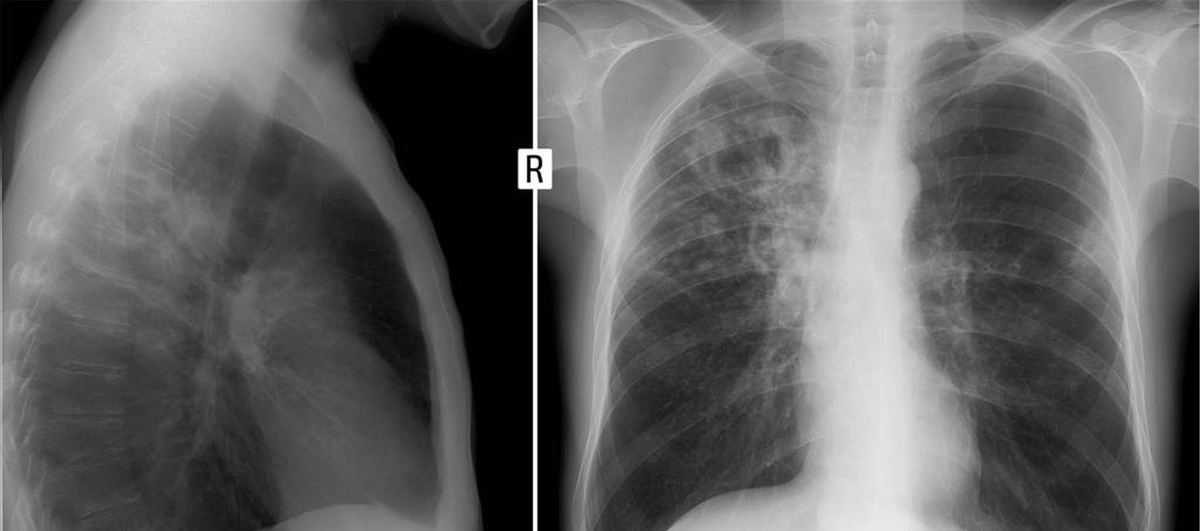

这事要从2019年说起,当时王大爷被诊断出肺部有结节,大小在1cm左右,医生建议他保守治疗。随即医生了解到王大爷的生活习惯很差,每天要抽一包香烟,于是医生告诫他如果再继续抽烟,那么这处结节就有可能演变为肺癌。

当这些固体颗粒物进入肺部后能完全堵塞肺泡,从而影响肺部的扩张,像上文的王大爷,本来就有肺结节,如果继续吸茶烟,那么结节会越来越大,加快肺癌的进程。